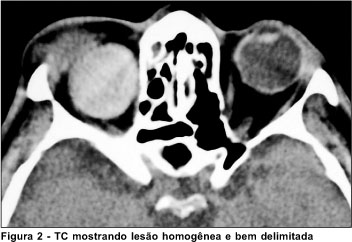

Avaliação clínica e laboratorial detalhada, incluindo hemograma, glicemia de jejum, eletroforese de proteínas, velocidade de hemossedimentação, fator antinuclear e Raios-X de tórax não mostrou alterações. A Tomografia Computadorizada (TC) de crânio e órbitas evidenciou lesão bem delimitada, de conteúdo homogêneo, sem realce com contraste venoso, de cerca de 2,7 cm situado na região intraconal da órbita direita (Figura 2). A ultra-sonografia mostrou uma massa homogênea cística, com interior de baixa refletividade, sugerindo um conteúdo líquido no interior da lesão. Foram feitas as hipóteses diagnósticas de cisto hemático, abscesso orbital, infecção parasitária (cisto hidático), além de um tumor orbitário com componente cístico em seu interior.

Dentro do diagnóstico diferencial devemos incluir outras lesões císticas da órbita tais como: cisto dermóide, teratoma, mucocele, encefalocele e cisto hidatiforme da órbita, além de outros tumores orbitários como o linfangioma, o hemangioma cavernoso, o neurilemoma, o neurofibroma etc. Os exames de imagem são extremamente úteis para o diagnóstico diferencial. Nos casos de cisto hemático a tomografia computadorizada mostra uma lesão bem definida e homogênea da órbita. Tal achado é muito importante embora seja relativamente inespecífico podendo ocorrer em outras lesões tumorais acima mencionadas(9). A IRM por outro lado, representa o exame que melhor define o cisto hemático uma vez que permite a identificação e caracterização de diferentes etapas de hemorragias. Quando ocorre sangramento recente a hemoglobina (na forma de desoxihemoglobina) é bem visibilizada como uma imagem hipointensa em T2. Já na fase subaguda, ocorre a transformação de hemoglobina em metahemoglobina que se mostra hiperintensa em T1 e também hiperintensa em T2. Por fim, na fase crônica, a hemossiderina derivada da hemoglobina se mostra hipointensa em T1.